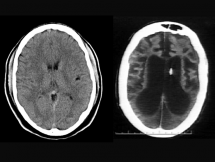

Brain Damage from Lack of Oxygen